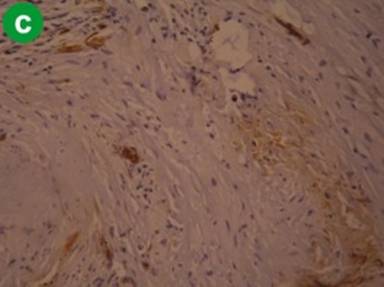

Adenocarcinoma of the Pancreas

H&E staining showed poorly oriented cells infiltrating singly, to solid sheets of neoplastic cells, ductal proliferation, clusters of proliferative acini with loss of lobular architecture, invasive adenocarcinoma, nuclear pleomorphism, necrotic debris and increased stroma, in variable combinations and frequency (Figure 3a). Immunohistochemistry with α-SMA showed dense and diffuse staining pattern in areas of fibrosis, denser in visual impression compared to tropical calcific pancreatitis and alcoholic chronic pancreatitis (Figure 3b). Staining with CD34 showed no or sparse positivity in the areas of fibrosis, but staining was present in blood vessels and ducts (Figure 3c). These findings suggest that activated stellate cells are diffusely present in the areas of desmoplasia.

Figure 3. Representative staining pattern observed in cases of adenocarcinoma of pancreas (a. H&E, b. α-SMA, c. CD34). |